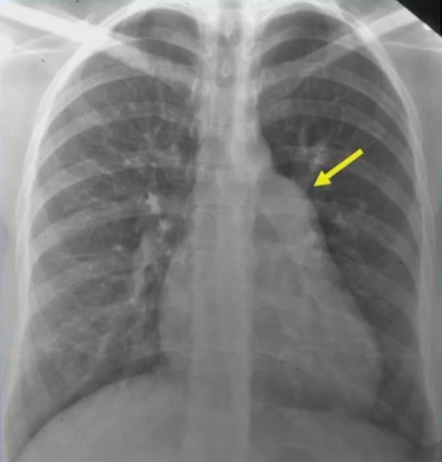

- CXR: Prominent PA, RA, RV, pulmonary plethora

Associated findings: Secundum ASD

Prominant PA

Pulmonary plethora